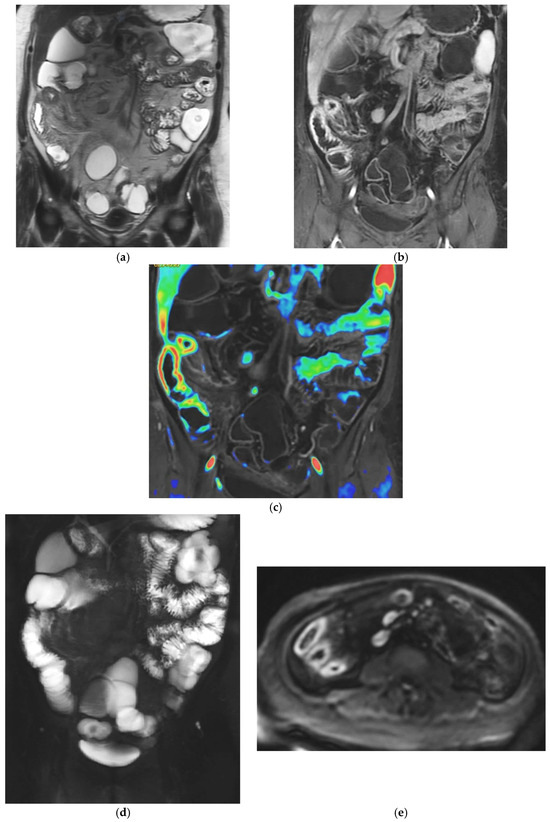

Figure 2.

47-year-old female patient with recurrent ileal Crohn’s disease following resection. (a) Coronal T2-weighted image demonstrating recurrent ileal Crohn’s disease at the anastomotic site, characterized by marked bowel wall oedema. (b) Corresponding axial T1-weighted image after gadolinium administration showing intense mural hyperenhancement of the affected ileal loop. (c) Post-processed color-coded map derived from the T1-weighted gadolinium-enhanced sequence, with areas of maximal enhancement highlighted in red. (d) Single-shot fast spin-echo sequence with follow-through–like appearance, clearly depicting the lumen of both normal and pathological small-bowel loops. (e) Axial diffusion-weighted imaging (DWI) showing marked diffusion restriction within the diseased ileal segment.